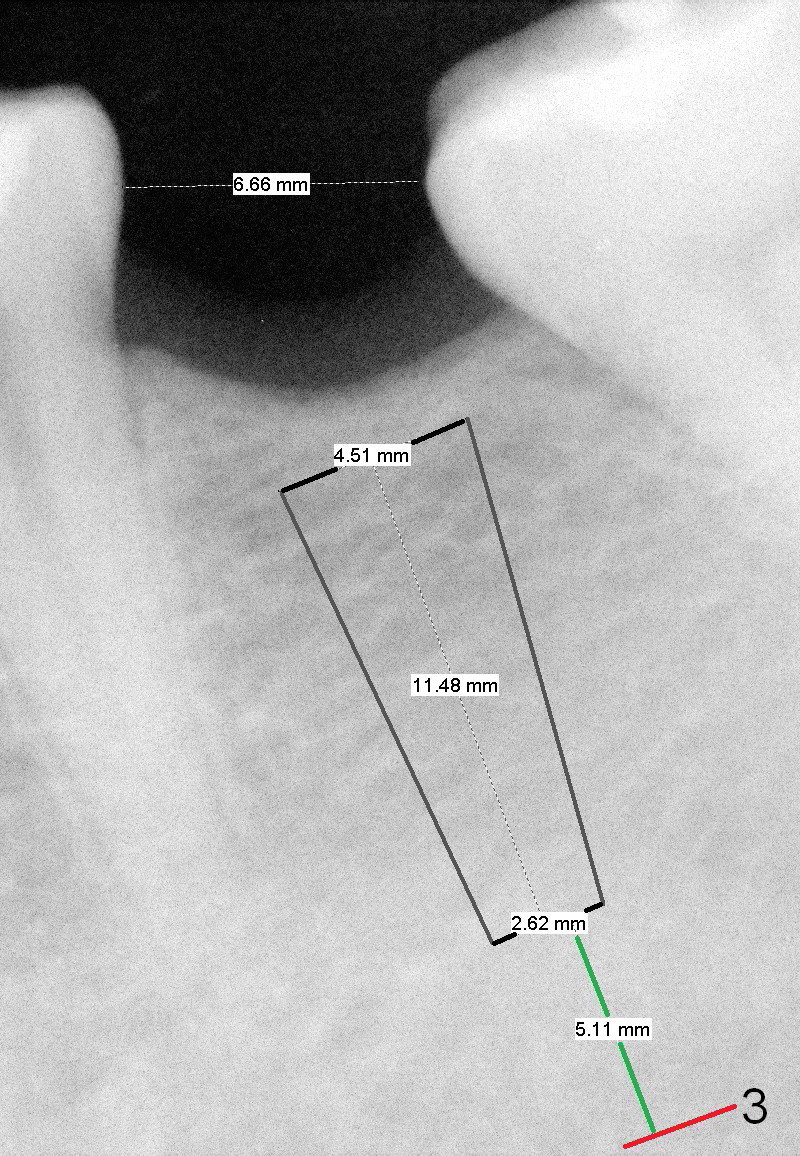

A 31-year-old woman agrees to have implant at #19 (Fig.1) after redoing MOL composite at #20 (Fig.2 *). The edentulous mesiodistal space is narrow (~ 6 mm in Fig.3). If the buccolingual bone width is found to be good after incision, a large implant is preferred. To gain space mesiodistally, the proximal surfaces of the neighboring teeth will be reduced (Fig.2 blue curved lines).

In fact, the buccolingual width of the ridge is sufficient to have a 4.5x11.5 mm implant placed (Fig.4,5, D3 bone, <35 Ncm). Proximal reduction is done before and after placement of a 5.5x4(3) mm abutment. Heavy abutment height adjustment is provided as well as the opposing prior to immediate provisional.